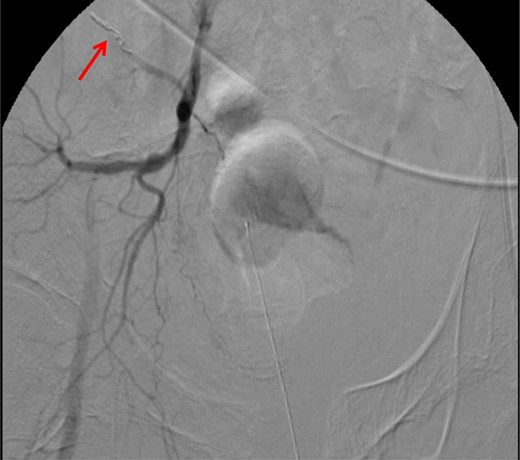

CT abdomen/pelvis with contrast was performed and a blush of contrast was noted posterior to the right pubic bone. Prior to taking patient for exploratory surgery, he was transferred to the interventional radiology suite where a pelvic angiogram was performed revealing an abnormal blush localized to the distal branches of the right iliolumbar artery (Fig. 2). Delayed phase of the angiogram demonstrated early venous filling consistent with a traumatic arteriovenous fistula which was embolized with 300–500 µ of embospheres and three 3 × 2 microcoils (Figs 3 and 4).

CT angiogram demonstrating microcoil embolization of AV fistula.

CT angiogram demonstrating successful embolization of AV fistula.

After resolution of the traumatic arteriovenous fistula (Fig. 2), a second blush from the right distal internal pudendal artery was identified and successfully treated with Gelfoam slurry. Subsequently, patient underwent exploratory laparotomy which revealed mesenteric and retroperitoneal hematomas. He also underwent craniotomy for evacuation of the subdural hematoma and open reduction internal fixation of the anterior and posterior pelvis. After discharge in fair condition to a subacute rehabilitation facility, patient developed a deep venous thrombosis managed by Coumadin.